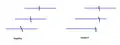

Line cancellation neglect test Line cancellation neglect test result

Line cancellation neglect test result The Allochiria phenomena might be revealed by the request to draw a clock.

The Allochiria phenomena might be revealed by the request to draw a clock. The patients has to mark the half of the line.

The patients has to mark the half of the line.

In order to assess not only the type but also the severity of neglect, doctors employ a variety of tests, most of which are carried out at the patient's bedside. Perhaps one of the most-used and quickest is the line bisection. In this test, a line a few inches long is drawn on a piece of paper and the patient is then asked to dissect the line at the midpoint. Patients exhibiting, for example, left-sided neglect will exhibit a rightward deviation of the line's true midpoint.[6]

Another widely used test is the line cancellation test. Here, a patient is presented with a piece of paper that has various lines scattered across it and is asked to mark each of the lines. Patients who exhibit left-sided neglect will completely ignore all lines on the left side of the paper.[6]